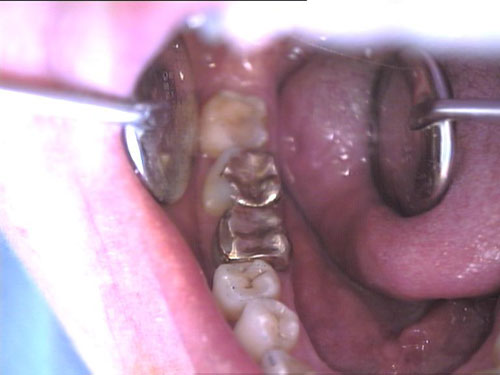

Goldinlay